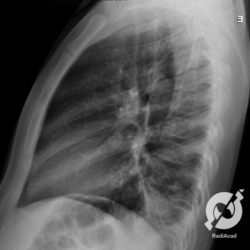

Os agentes etiológicos infecciosos são variados (bactérias, vírus, fungos, parasitas…), mas o que ocorre nos pulmões durante uma infecção por qualquer tipo de agente é a substituição do ar alveolar por secreção (pus, muco, eventualmente sangue ou necrose…) e com isso a manifestação radiográfica vai ser a mesma já que todas estas secreções apresentam a mesma densidade radiográfica: partes moles.

E o nome dado a esta alteração radiográfica que corresponde à substituição do ar alveolar por líquido é a consolidação alveolar.

Uma consolidação alveolar é, por definição, uma opacidade (imagem densa, branquinha) homogênea ou às vezes heterogênea (pela presença de calcificações ou cavidades), de limites mal definidos, exceto quando toca a pleura da parede ou das cissuras pulmonares. É um termo usado tanto em radiografia, como em tomografia computadorizada. Na tomografia, um outro termo é usado: vidro fosco, que é uma opacidade (branquinha mas não tanto como a consolidação), que borra o pulmão mas deixa ver os vasos de permeio (igual bigode de adolescente: dá pra ver todo o fundo).

Nós vamos mostrar aqui um pequeno apanhado de pneumonias de variados agentes, em diversos segmentos e lobos pulmonares, com extensões variadas. O objetivo é identificar o padrão radiológico de consolidação alveolar e não determinar o agente infeccioso, isso vai ser assunto para mais adiante. Aliás já antecipo que é fundamental saber localizar a lesão, porque alguns destes bichos gostam de determinados segmentos, alguns tumores também têm as suas preferências, então localização é fundamental. Se localização não fosse importante, um apartamento na beira do mar sairia o mesmo preço de um apartamento de frente pra BR-101, concordam?

Seguem alguns dos nossos casos de pneumonia para vocês treinarem os olhos e não se apavorarem nos plantões.